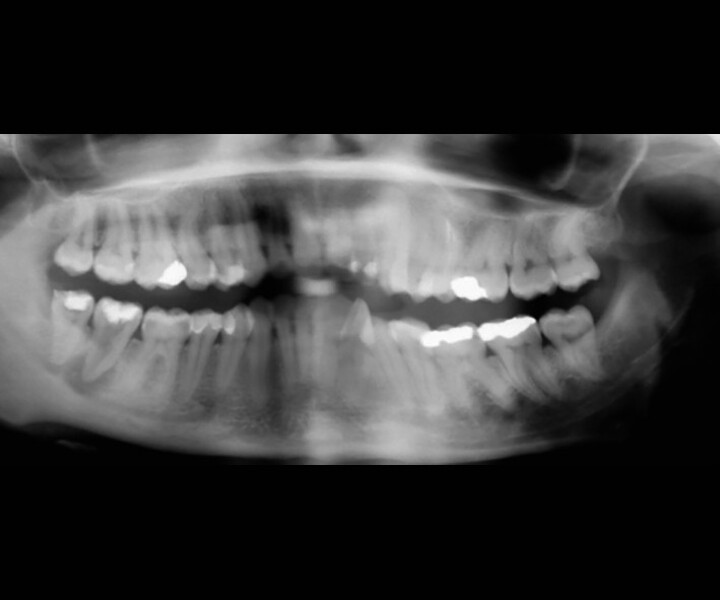

Fig. 4: Pre-op CBCT scan, pseudo-panoramic view.